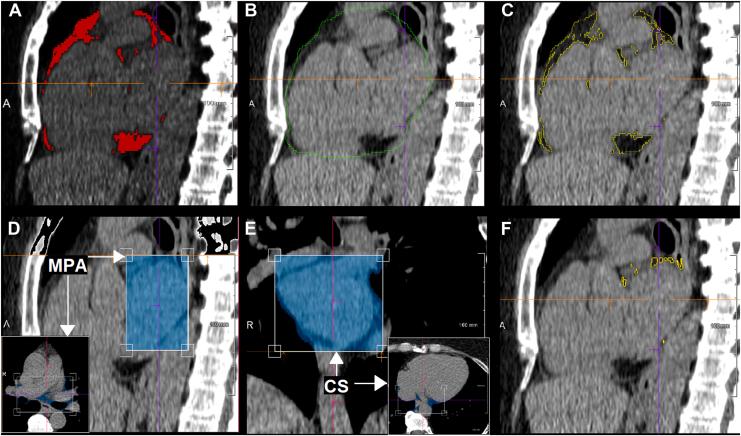

Retrospective matched case-control study of patients with and without AF, undergoing noncontrast electrocardiographic (ECG)-gated cardiac computed tomography (CT). Segmentation of LA-EAT and extraction of LA-EAT radiomic features were performed using syngo.via Frontier (Siemens Healthineers, Forchheim, Germany). Univariate analysis identified radiomic features associated with AF. Predictive models for AF were developed via logistic regression and machine learning-based random forest analyses. Models were validated on external cohort of patients with 1:1 AF : control ratio and deployed in a real-world setting with an AF : control ratio of 15:85.

对接受非增强心电图(ECG)门控心脏计算机断层扫描(CT)的AF患者和非AF患者进行回顾性匹配病例对照研究。使用syngo.via Frontier(德国福希海姆西门子医疗公司)对LA-EAT进行分割并提取LA-EAT放射组学特征。单因素分析确定与AF相关的放射组学特征。通过逻辑回归和基于机器学习的随机森林分析开发AF预测模型。模型在AF与对照比例为1:1的外部患者队列中进行验证,并在AF与对照比例为15:85的真实环境中应用。